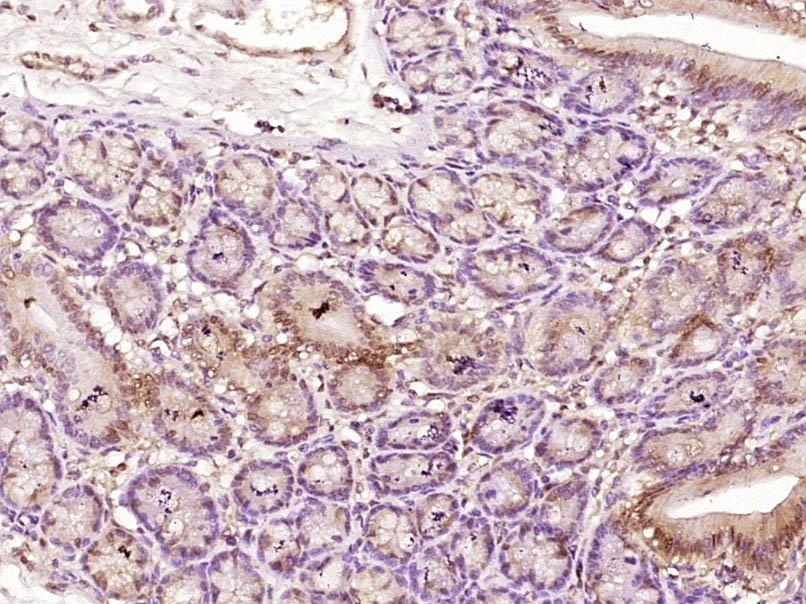

Paraformaldehyde-fixed, paraffin embedded (Human colon carcinoma); Antigen retrieval by boiling in sodium citrate buffer (pH6.0) for 15min; Block endogenous peroxidase by 3% hydrogen peroxide for 20 minutes; Blocking buffer (normal goat serum) at 37°C for 30min; Antibody incubation with (MSH6) Polyclonal Antibody, Unconjugated (bs-3804R) at 1:400 overnight at 4°C, followed by operating according to SP Kit(Rabbit) (sp-0023) instructionsand DAB staining.